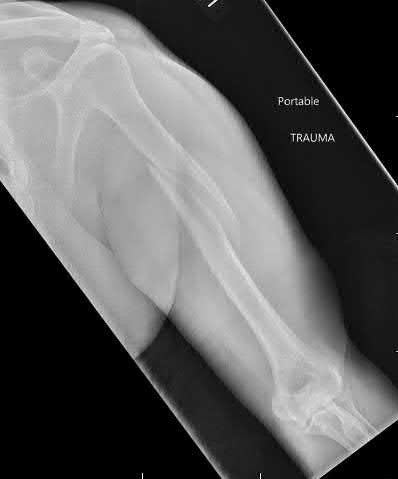

Question 3:

A 15-year-old boy presents with a permeative lytic lesion in the femoral diaphysis with aggressive periosteal reaction ('onion skinning'). Biopsy reveals uniform small round blue cells. Cytogenetic analysis of this tumor will most likely demonstrate which of the following translocations?

Correct Answer: t(11;22)

Explanation:

The clinical and radiographic description is classic for Ewing sarcoma. The characteristic cytogenetic abnormality is a balanced translocation t(11;22)(q24;q12), which fuses the EWS gene on chromosome 22 with the FLI1 gene on chromosome 11. This is seen in approximately 85-90% of Ewing sarcomas. t(9;22) is the Philadelphia chromosome (CML), t(X;18) is seen in synovial sarcoma, t(2;13) in alveolar rhabdomyosarcoma, and t(12;16) in myxoid liposarcoma.